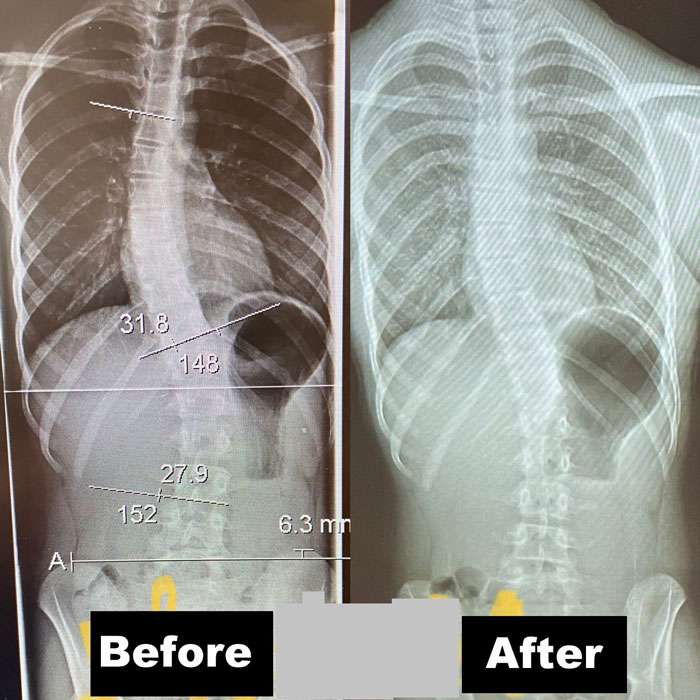

Scoliosis is measured on x-ray as a Cobb Angle. This measurement tells us how bad the scoliosis is and then guides us in how we treat it. Curves under 10 degrees usually aren’t considered scoliosis. Those curves 10-25 are called mild curves and we treat them with scoliosis specific exercise. Curves 25-45 degrees are treated with scoliosis specific exercise and bracing. Those above 45 degrees are usually surgical candidates. There is a measurement error of 3-5 degrees, which means to really have significant change, it needs to be above that.

Here are some examples of what can be done with scoliosis specific exercise with a variety of patients. The main goal of treatment is to STOP progression of the curve. With hard work and dedication we can also see reduction in the curve.